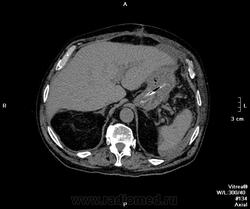

Пациент поступил ко мне через 6 дней после ушивания перфоративной язвы ДПК. УЗИ-сты увидели инфильтративно-жидкостные изменения в зоне оперативного вмешательства, пузырьки газа. Но смутило найденное образование в пространстве между правой долей печени и паранефрием. цель исследования - дифференцировать найденное между инфильтрацией и жидкостным скоплением.

Пациента готовили в течение 2 часов, перорально разведенный урографинчик дробно, и пол станканчика перед исследованием (это важно). Болюс в артериальную и венозную фазы.

мы имеем - задренированное околопеченочное пространство, жидкость в подпеченочном, левом поддиафрагмальном пространстве и по контурам селезенки (серозная), к передне-наружному контуру левой доли печени прилежит ограниченное жидкостное скопление

-ничего криминального между висцеральной поверхностью печени и правой почкой (паранефрий как им угодно) не вижу

-!!! в нативе желудок и петли кишечника не контрастированы - следы контраста в отдельных петлях тонкого к-ка (перед исследованиям он пил, по зонду ничего никуда - ни ни!!!), петли толстого и тонкого кишечника содержат умеренно повышенное количество воздуха и жидкого содержимого, с горизонтальными уровнями

- просвет верхне-горизонтальной ветви дпк в области оперативного вмешательства и зоны сегментарной пластики убудительно не прослеживаеся, представлен зоной инфильтрации, утолщенными стенками кишки, по наружному контуру воспаленных тканей лентовидно расположенные пузырьки воздуха - более вероятно воздух на фоне складок; затеков КВ нет

- воспалительные изменения в проекции лапаротомного доступа, в пжк передней брюшной стенки, в абдоминальной жировой клетчатке и межпетельно

- диверткулище мочевого пузыря

- инфильтрат в левой седалищно-прямокишечной ямке

- меня смущает не типичный вид артериальной фазы, и уж тем более венозной

Усиление коркового вещества слабое, задержка начала нефрографической фазы. диаметр почечным артерий около 5 мм, почечных вен -- 10мм. на 60 секунде отсутствует должное конрастирование вен, без признаков патологического сброса

Случай 1. Атеросклероз сосудов, запаздывание фаз секунд на 20-25. Получили раннюю артериальную фазу (посмотрите контрастирование камер сердца). И вместо портальной - нечто между поздней артериальной и портальной. Стоило, как мне кажется, сделать 85-90 сек, тогда бы попали в порталку.

По поводу жидкостей в брюшной полости (инфильтраты? где? Виталий показывает скопление жидкости у левой венечной связки) - нормальное послеоперационное их распределение, результат самой операции - т.е. лизированная кровь, ничего криминального, в соответствии с анатомией связок (в том числе и левой венечной, селезеночно-ободочной, желудочно-диафрагмальной)), обычная п/о реакция клетчатки. Абсцессов нет.